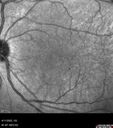

40 year old man About 10 days ago the patient woke up with a dark circle in the middle of the left eye that blocks his vision. He thought it might be from fatigue. The month of March was very stressful. After a few days the spot in the left eye got darker and he could not drive at night. During the last week while not going to work and sleeping more his vision is better but not normal. He has never had vision loss in the past. Â

PMHx: Benign, Meds: Multivitamin

VA OD: sc20/16 NscJ1+VA OS: sc20/32+2 NscJ4

IOP: TP: OD:12 OS:12